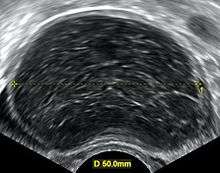

Ovarian cysts are considered large when they are over 5 cm and giant when they are over 15 cm. In children ovarian cysts reaching above the level of the umbilicus are considered giant.

Ovarian cysts are usually diagnosed by either ultrasound, CT scan or MRI, and correlated with clinical presentation and endocrinologic tests as appropriate.

Follow-up imaging in women of reproductive age for incidentally discovered simple cysts on ultrasound is not needed until 5 cm, as these are usually normal ovarian follicles. For simple cysts greater than 5 cm but less than 7 cm in premenopausal females, cysts should be followed yearly. For simple cysts greater than 7 cm, further imaging with MRI or surgical assessment is mandated as, because of their large size, these cysts cannot be reliably assessed by ultrasound alone. The primary concern for larger cysts is the potential for non-visualization of soft tissue nodularity or thickened septation at their posterior wall due to limited penetrance of the ultrasound beam. For the corpus luteum, a dominant ovulating follicle that typically appears as a cyst with circumferentially thickened walls and crenulated inner margins, follow up is not needed if the cyst is less than 3 cm in diameter. In postmenopausal patients, any simple cyst greater than 1 cm but less than 7 cm needs yearly follow-up, while those greater than 7 cm need MRI or surgical evaluation, similar to reproductive age females.[8]